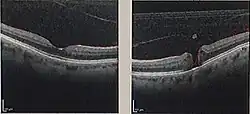

| Optical coherence tomography (OCT) of a macular hole (right) as compared to a normal macula. | |